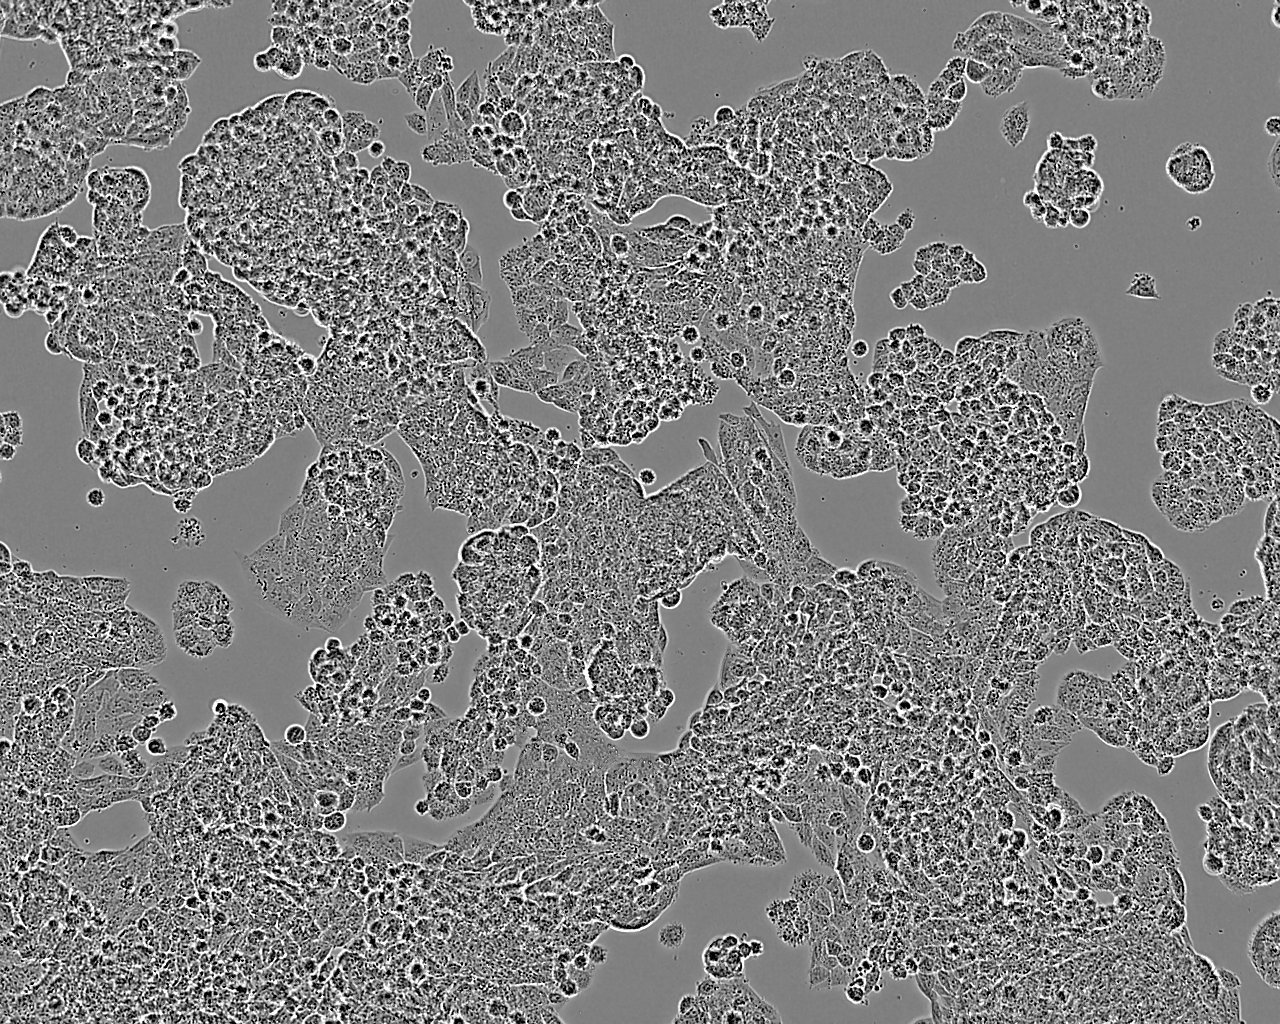

特征特性 从一位未接受治疗的患者的癌组织中分离建系。细胞会单层生长,在摇床培养时可悬浮生长。可用作抗药药物敏感性研究模型。

形态特征 上皮细胞样

生长特征 贴壁